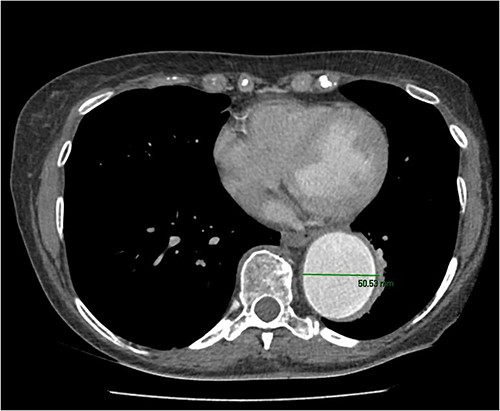

A 67-year-old female with a history from renal impairment and chronic obstructive pulmonary disease (COPD) as an ex-smoker, presented with a known type 2 TAA. A CT aorta showed an aneurysm starting from the left subclavian artery to the aorto-iliac bifurcation. This measured 52 mm in diameter distally near the bifurcation and 50 mm at the descending aorta. Similarly, the distal aortic arch was dilated at 35–40 mm, and the distal ascending aorta was 45 mm and calcified (Fig. 1).